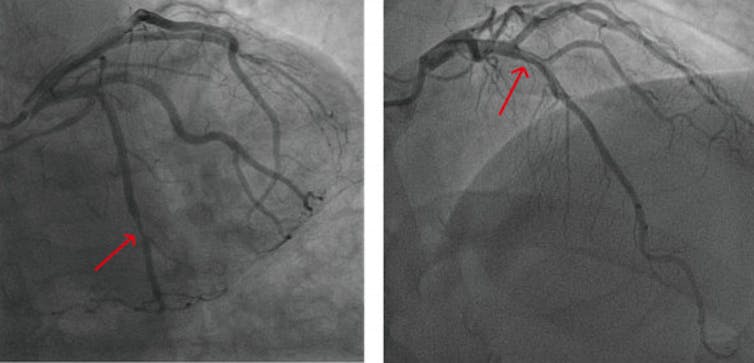

Women are more likely than men to have cardiovascular disease that presents as multiple narrowed arteries that are not fully “clogged,” resulting in chest pain because blood flow can’t ratchet up enough to meet higher oxygen demands with exercise, much like a low-flow showerhead. When chest pain presents in this way, doctors call this condition ischemia and no obstructive coronary arteries. In comparison, men are more likely to have a “clogged” artery in a concentrated area that can be opened up with a stent or with cardiac bypass surgery. Options for multiple narrowed arteries have lagged behind treatment options for typical “clogged” arteries, which puts women at a disadvantage.

Blood vessels don’t need to be clogged by plaque to cause heart disease. Zhao and Gong 2023/Mathematical Biosciences and Engineering